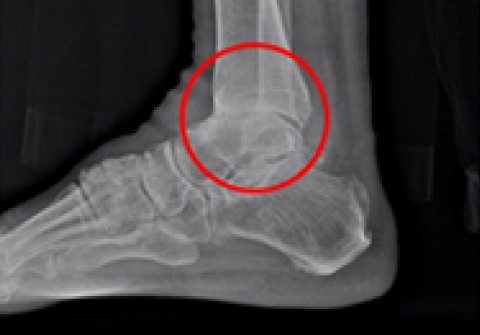

발목 인공관절 수술

2016.11.01

2017.02.01